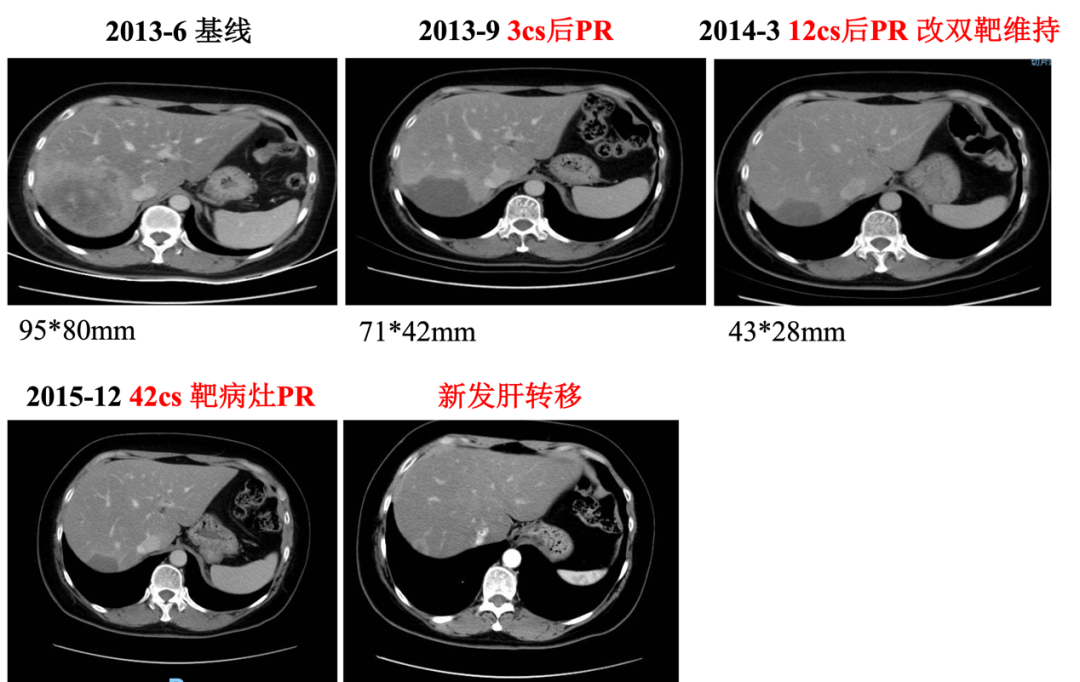

▌影像学检查:

2013年6月30日腹部CT:肝右后叶病灶并肝内多发子灶,考虑M,病灶总范围8.0*5.8cm,其病灶周围可见多发异常廓清子灶(4-5个),最大约1.6cm;

图1. 腹部CT

▌一线治疗:

入组MO28047临床试验(PERUSE研究),于2013-7-16开始行紫杉醇+曲妥珠单抗+帕妥珠单抗方案治疗,具体:紫杉醇175mg/m2 270mg d1;帕妥珠单抗首剂840mg,以后420mg d1;曲妥珠单抗首剂 8mg/kg 484mg,以后6mg/kg 363mg d1,Q21d。最佳疗效PR,自第10周期调整为双靶维持治疗。2015年12月(42周期时)原靶病灶维持PR,新发18mm肝转移,评效病情进展,PFS为30月。不良反应:腹泻2级,粒细胞下降2级。

图2. 一线治疗